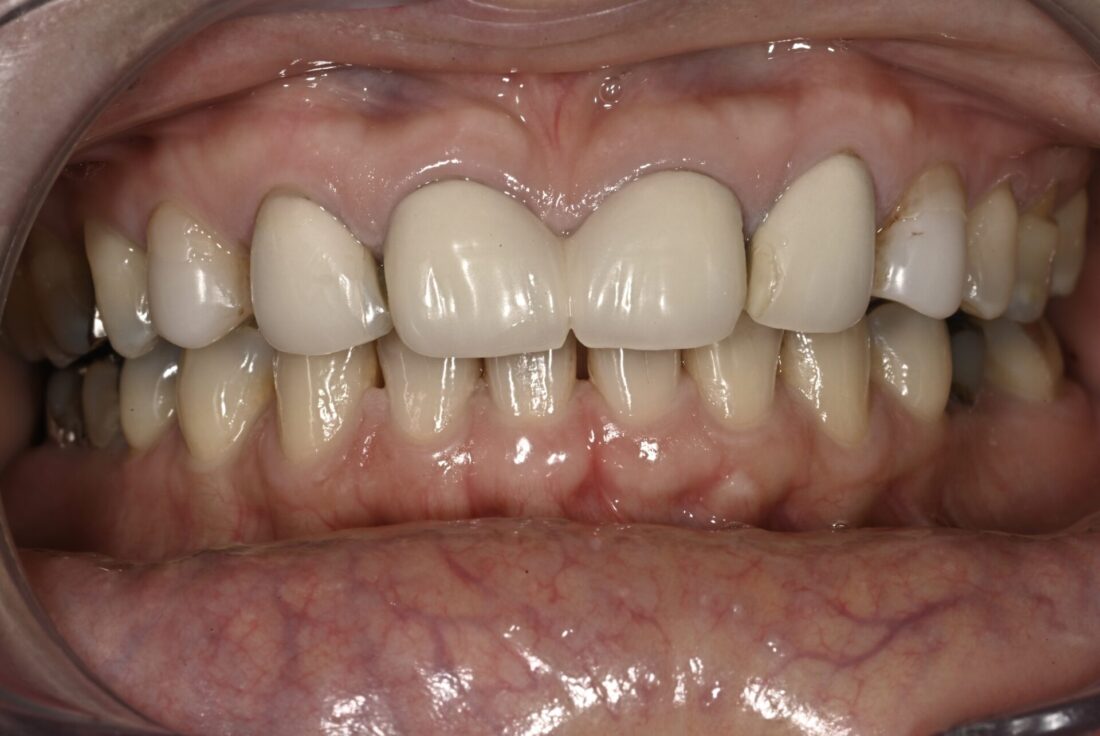

術前

患者さんは元々上顎左右側切歯(2┛┗2)先天的欠如で隙間が開いている状態で、それが気になるということで、「セラミック矯正で有名」な歯科医院を受診、治療されたそうです。最初は隙間が無くなって満足されていた、、、、、というか、まあこんなものか、、、という感じだったらしいです。しかしながらご家族や周囲の方から歯が大きすぎるのではないかとの指摘を多数受け、気になりだしたので当院受診となりました。確かに私が考える「審美」には程遠い状態です。また、処置を始めるにあたり診査、診断を行ったところ他にも歯周病、根管治療、咬合など多数の問題がそのままであり、特に奥歯に関しては保存できない歯牙が多数ありましたが、前医では何の指摘もなかったそうです。現状ならびに治療計画を説明し、臼歯部は保存不可能な歯牙が多数あり、入れ歯もしくはインプラントによる治療が必要なこと、主訴である前歯に関しては矯正治療を組み入れないと審美的結果は得られないことを説明しました。